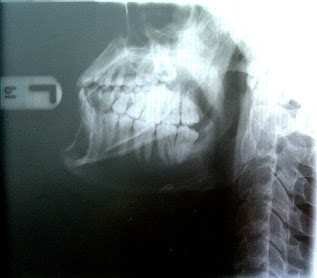

Kiefer mit Zähnen

Die heutige Ernährung, die sich von der ursprünglichen Ernährung der Jäger und Sammler stark unterscheidet, verursacht eine Ausbildung von kürzeren und schmaleren Unterkiefern, die dann oft nicht mehr genug Raum für die Zähne bieten und damit zu Zahnfehlstellungen führen. Dies liegt unter anderem an den Inhaltsstoffen, aber auch an der Konsistenz der Nahrung. Durch geringere Kaubewegungen bei zu weicher Nahrung werden die Knochen nicht genügend gestärkt. Der Rest des Schädels ist interessanterweise nicht betroffen.